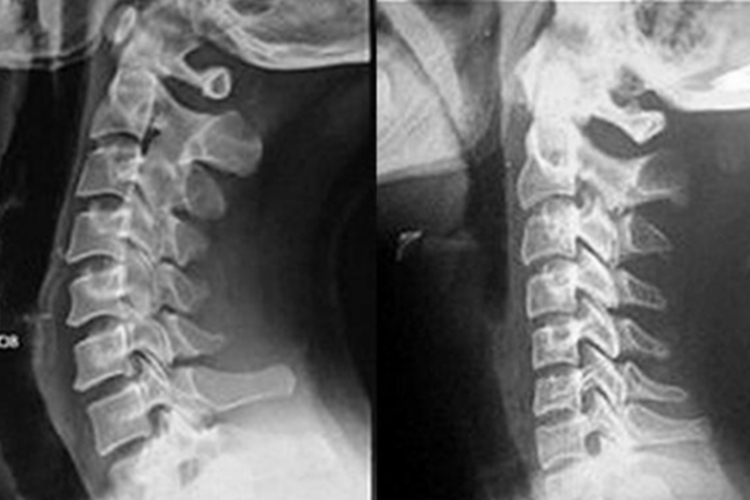

颈椎在正常情况下从侧方观察可见有一个生理性的曲度,颈椎生理曲度变直患者常常出现颈椎生理曲度消失,X线表现为变平、变直,甚至后凸,从而表现为脖子前倾。